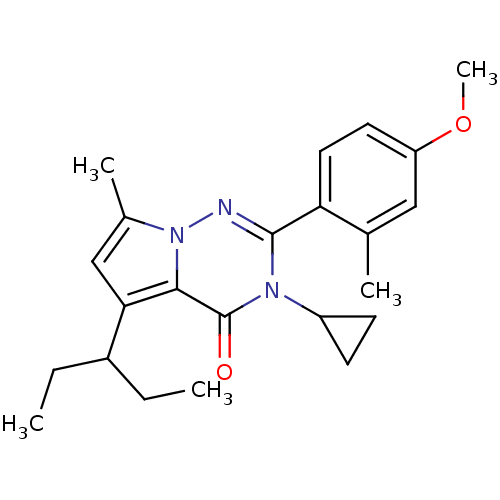

TargetCorticotropin-releasing factor receptor 1(Homo sapiens (Human))

Dupont Pharmaceuticals

Curated by ChEMBL

Dupont Pharmaceuticals

Curated by ChEMBL

Affinity DataEC50: 0.220nMAssay Description:Activity of peptidic agonists on corticotropin releasing factor receptor receptor using agonist-stimulated adenylate cyclase assayMore data for this Ligand-Target Pair